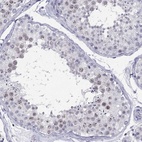

Immunohistochemical staining of human testis shows weak nuclear positivity in cells in seminiferous ducts.